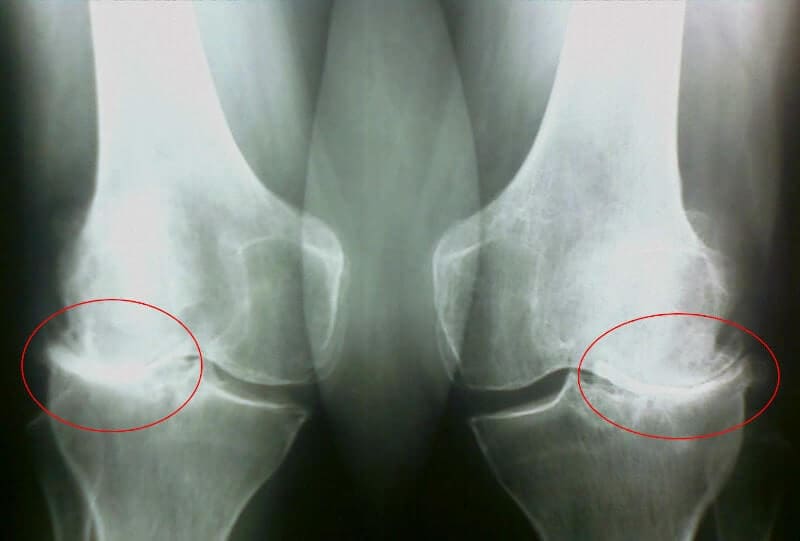

Bet aš turėjau eiti pas gydytoją, mano žmona to reikalavo. Terapeutas nusiuntė mane į reumatologą, į kurį man pavyko patekti per mėnesį, o eilė, bet ne vienas aš bendrauju su sąnariais,buvo daug tokių. Aš susipažinau su labai pagyvenusiu gydytoju, nieko nesakydamas, nusiuntė mane į rentgeno spindulius ir kraujo/šlapimo tyrimus. Per antrąjį susitikimą ji man per porą minučių diagnozavo - kažkokia artrozė, pirminė ar antrinė, dabar tiksliai nepamenu ir nesvarbu.

35 diena: išlaikiau testus ir pasidariau rentgeno nuotraukas. Jokių artrozės pėdsakų! Kremzlės sąnariuose kaip 30 metų. Specialistė sakė, kad ankstesnis rentgenas greičiausiai buvo su defektu, todėl artrozės diagnozė buvo klaidinga.